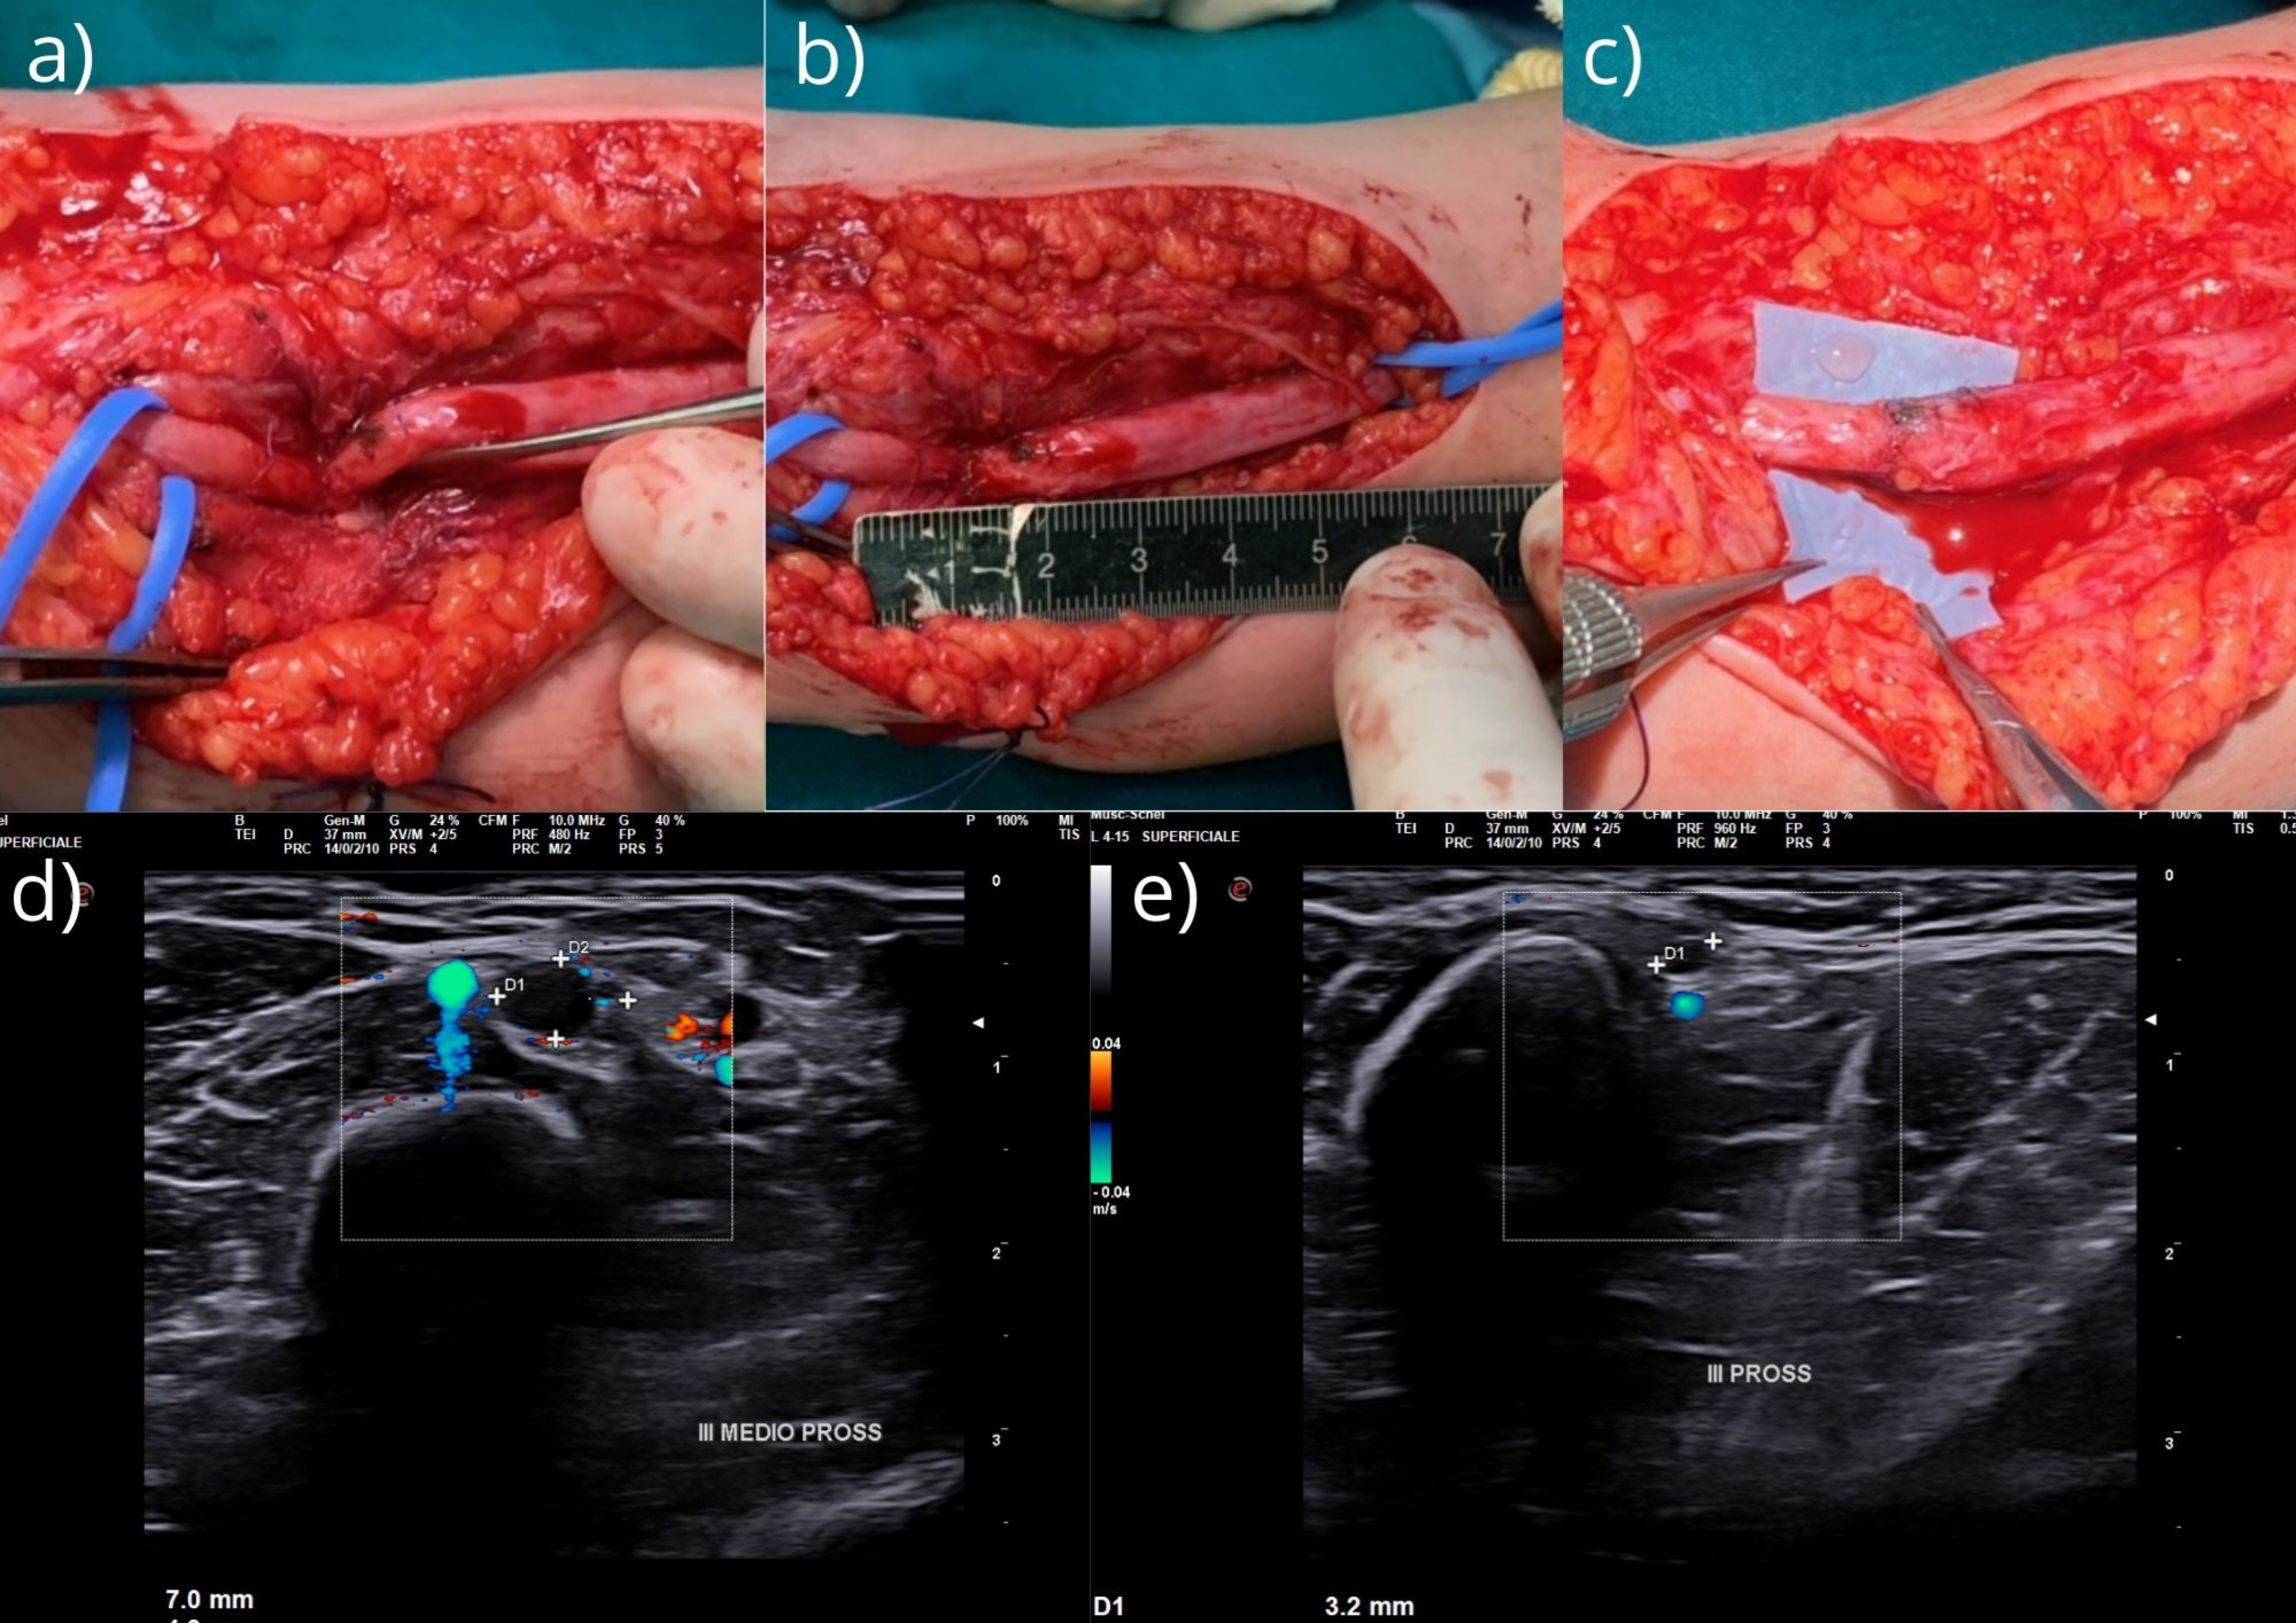

We opted for an immediate surgical exploration and treatment of the median nerve lesion at the fracture site; this was performed 6 months after the trauma occurred. Surgical exploration and dissection under the microscope allowed the nerve to be extracted from the bone callus and the fracture (Figure 2a); the nerve appeared to be completely kinked and incarcerated in the fracture callus. During careful dissection and excision of the scar tissue, the nerve was identified and released.

Figure 2.

(a) Median nerve incarcerated in the fracture site; (b) extension of the median nerve glioma; and (c) end-to-end suture and epiperineural suture with 9–0. Furthermore, a stitch of 7–0 in the epineural part of the nerve was proximally and distally placed 2 cm from the suture site to discharge the tension at the suture site. Intraoperative US: (d) nerve sufferance with peripheral edema (the maximum caliber was 24 mm) and (e) a sudden reduction in nerve caliber and interruption of its course at the volar margin of the humeral fracture.

Intraoperative nerve stimulation did not show any activation of muscles innervated by the median nerve, but the intraoperative US revealed complete transections of the fascicular pattern; only the epineurium tissue exhibited continuity (Figure 2d,e). The funicular pattern was proximally and distally present 1 cm from the lesion. Neurotomy with excision of the distal glioma and proximal neuroma was performed under magnification, and scar tissue was removed with a progressive slicing technique for the “normal” funicular pattern. At the end of the neurotomy, the substance loss was 2.5 cm (Figure 2b). We then freed the proximal and distal stumps for a distance of 3–4 cm on both sides and were able to avoid using grafts via end-to-end suturing of the nerve (microscope and epiperineural suture with 9–0) while flexing the elbow 30° (Figure 2c). Furthermore, a stitch of 7–0 in the epineural part of the nerve was proximally and distally placed 2 cm from the suture site to discharge the tension at the suture site [16]. We added fibrin glue at the end of the suture. The elbow was immobilized by a posterior splint flexed at 90° to protect the suture from any tension for 3 weeks; this angle was then progressively extended by 20 degrees per week up to complete extension. Rehabilitation was performed by a hand physiotherapist.